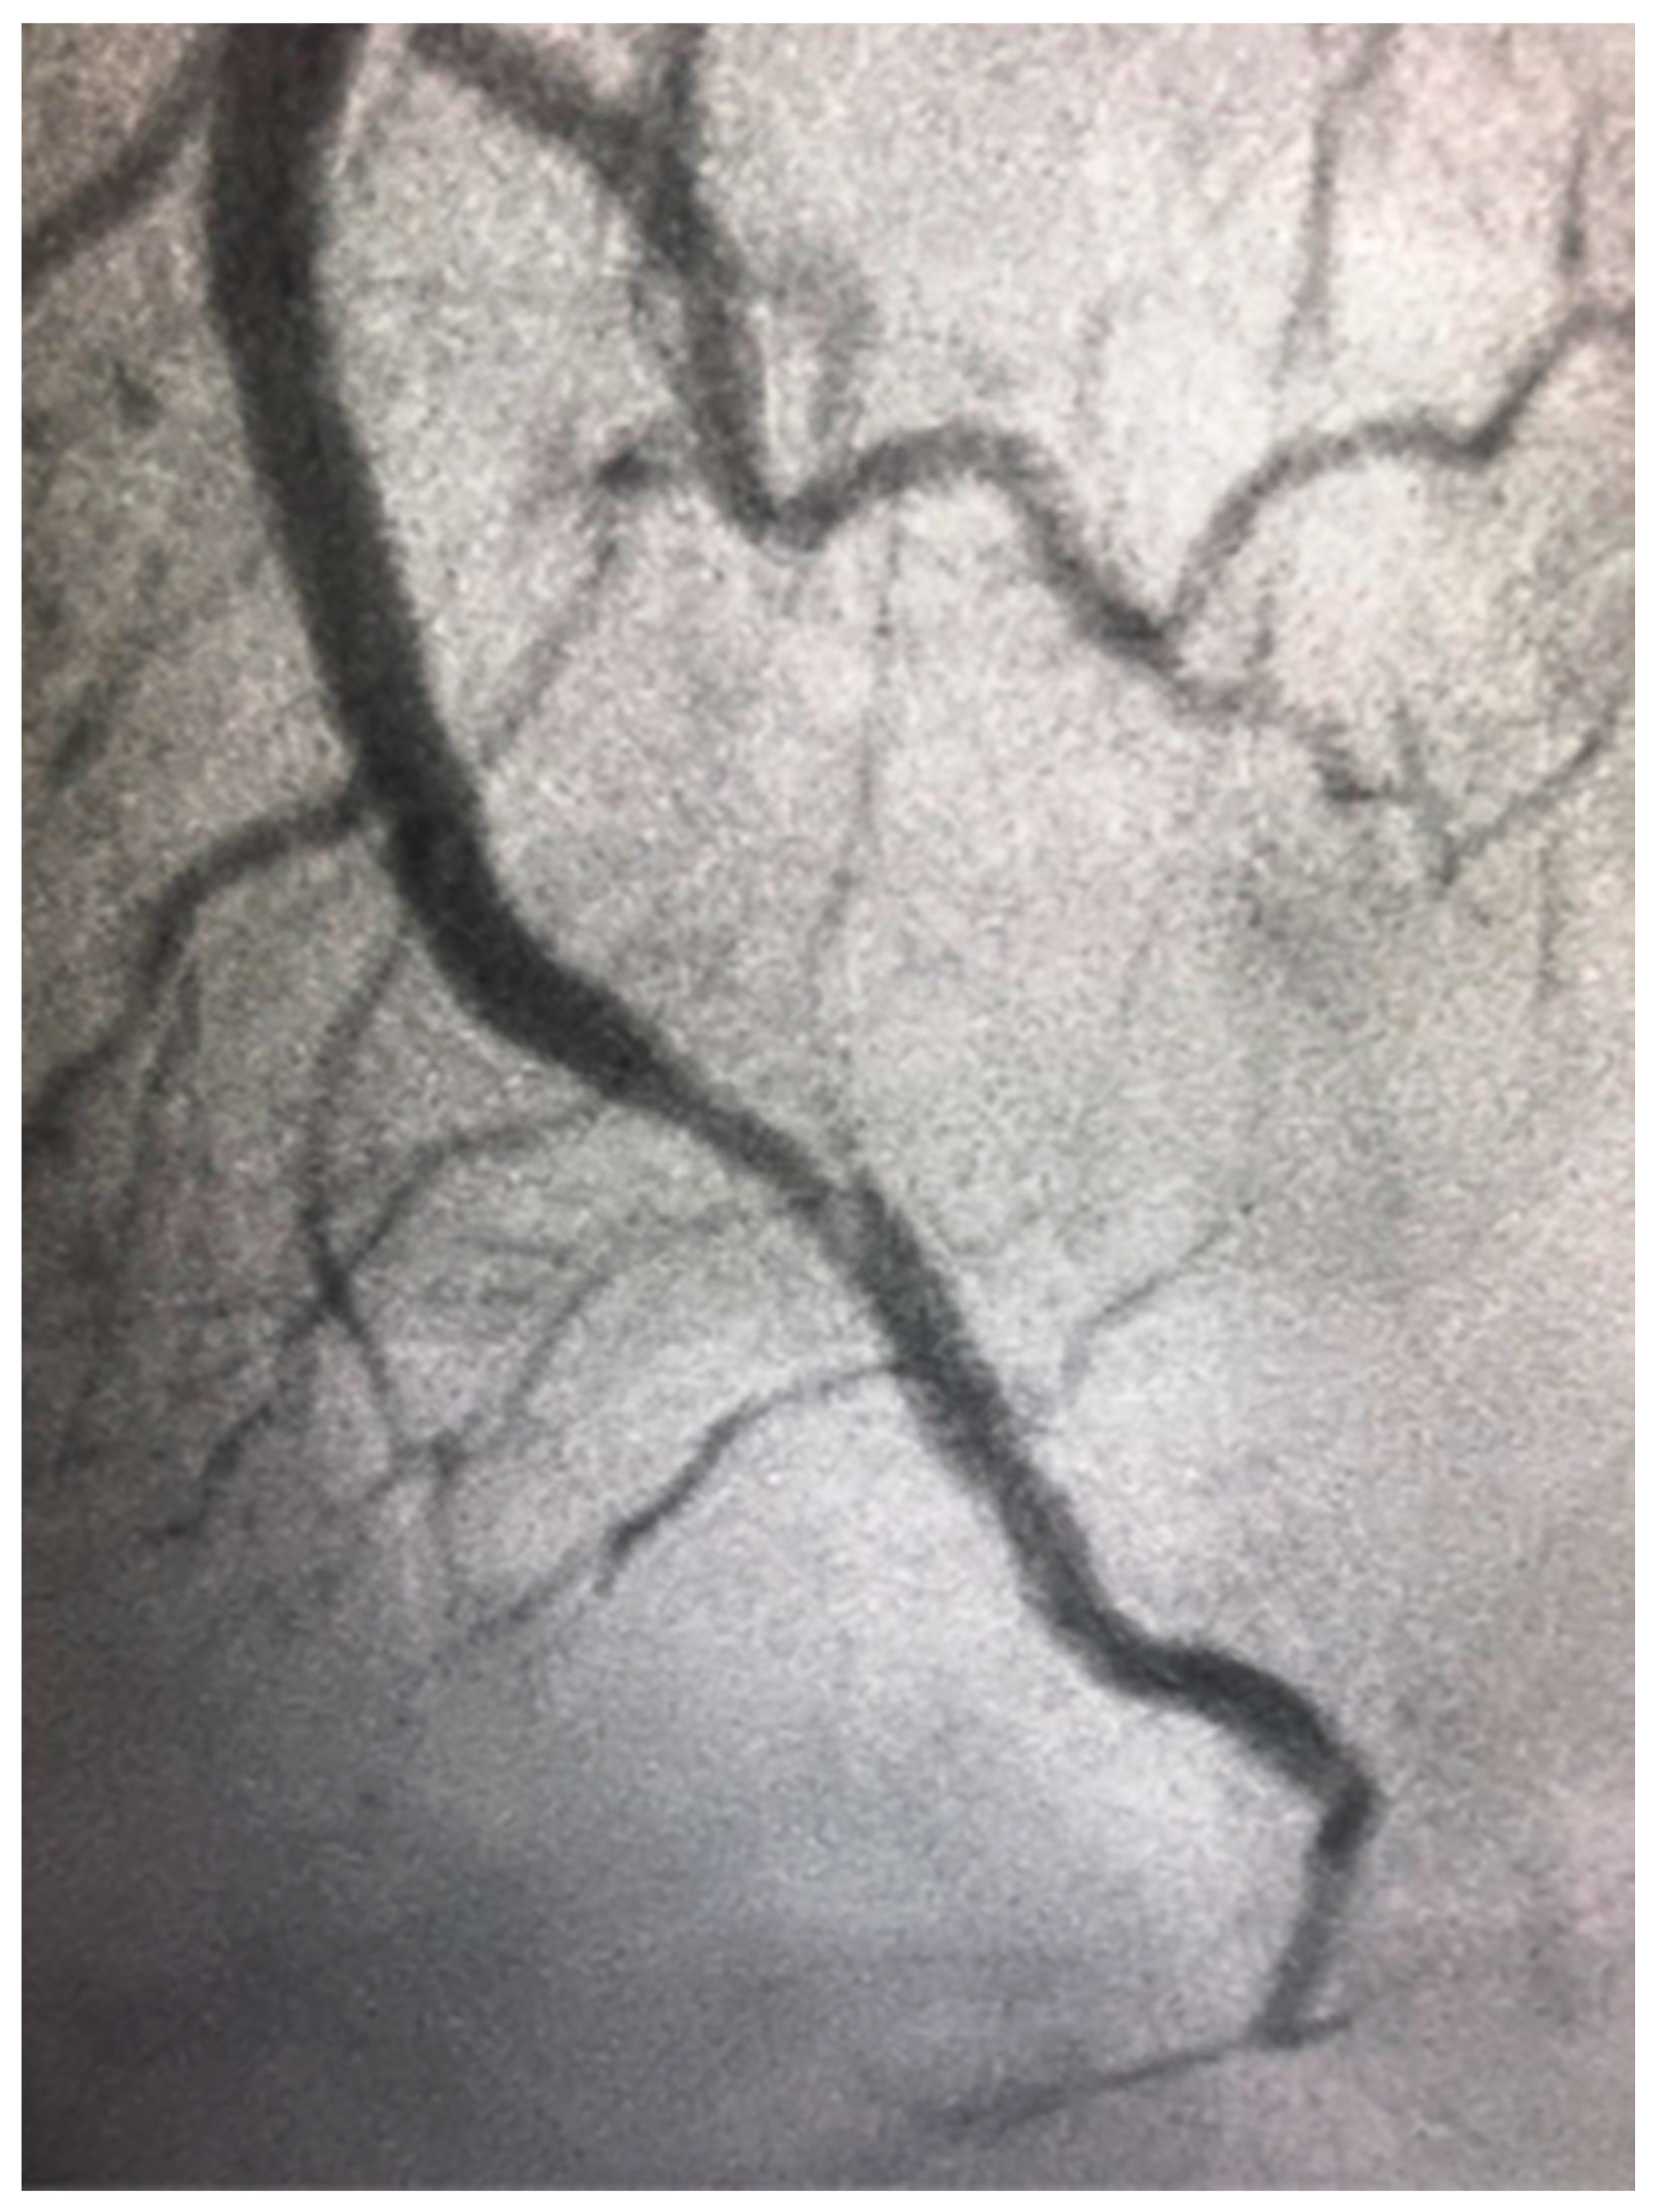

4.3. Obstructive CAD in Women

- Kornowski, R.; Lansky, A.J.; Mintz, G.S.; Kent, K.M.; Pichard, A.D.; Satler, L.F.; Bucher, T.A.; Popma, J.J.; Leon, M.B. Comparison of Men Versus Women in Cross-Sectional Area Luminal Narrowing, Quantity of Plaque, Presence of Calcium in Plaque, and Lumen Location in Coronary Arteries by Intravascular Ultrasound in Patients with Stable Angina Pectoris. Am. J. Cardiol. 1997, 79, 1601–1605. [Google Scholar] [CrossRef]